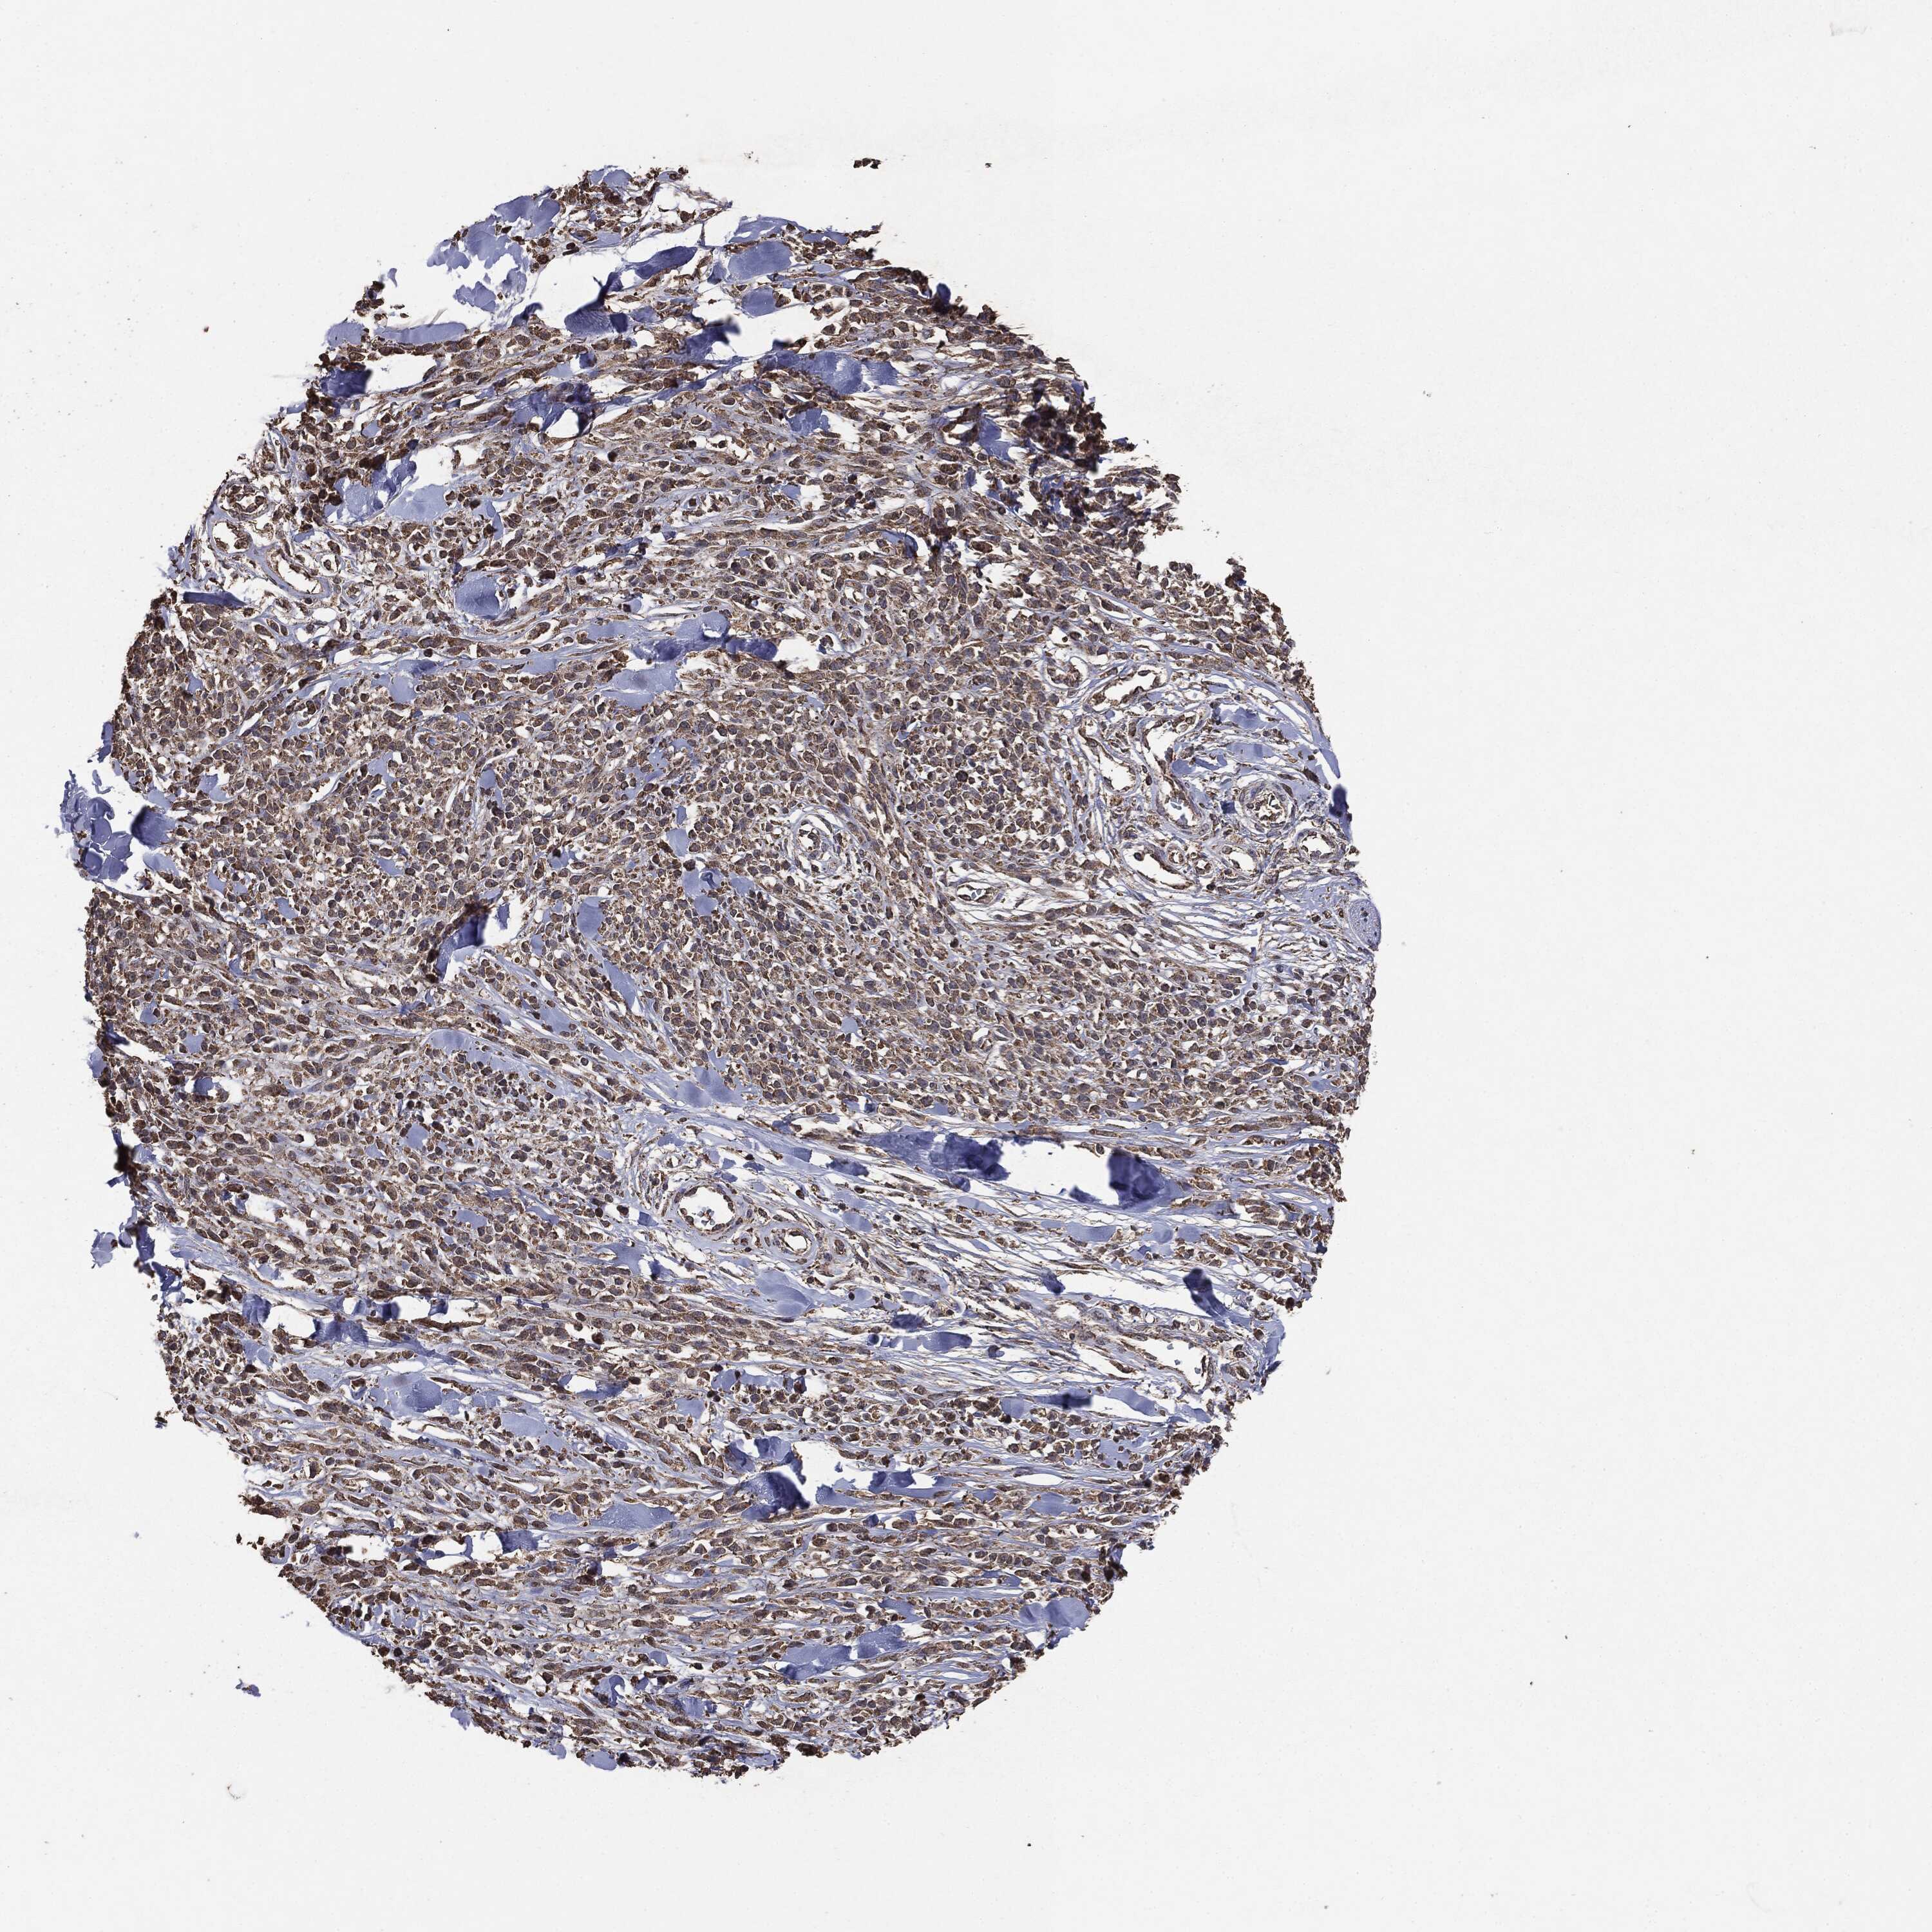

MELANOMA - Protein expressioni

A mouse-over function shows sample information and annotation data. Click on an image to view it in a full screen mode. Samples can be filtered based on level of antibody staining by selecting one or several of the following categories: high, medium, low and not detected. The assay and annotation is described here.

Note that samples used for immunohistochemistry by the Human Protein Atlas do not correspond to samples in the TCGA dataset.

Antibody stainingi

Antibody staining in the annotated cell types in the current human tissue is reported as not detected, low, medium, or high, based on conventional immunohistochemistry profiling in selected tissues. This score is based on the combination of the staining intensity and fraction of stained cells.

Each image is clickable and will lead to virtual microscopy that enables deeper exploration of all samples and also displays staining intensity scores, fraction scores and subcellular localization as well as patient and tissue information for each sample.

CAB069425

CAB080053

CAB080065

CAB080070

CAB080081

CAB080095

CAB080097

Staining

High

Medium

Low

Not detected

Intensity

Strong

Moderate

Weak

Negative

Quantity

>75%

75%-25%

<25%

None

Location

Nuclear

Cytoplasmic/membranous

Cytoplasmic/membranous,nuclear

Malignant melanoma, NOS

Malignant melanoma, Metastatic site